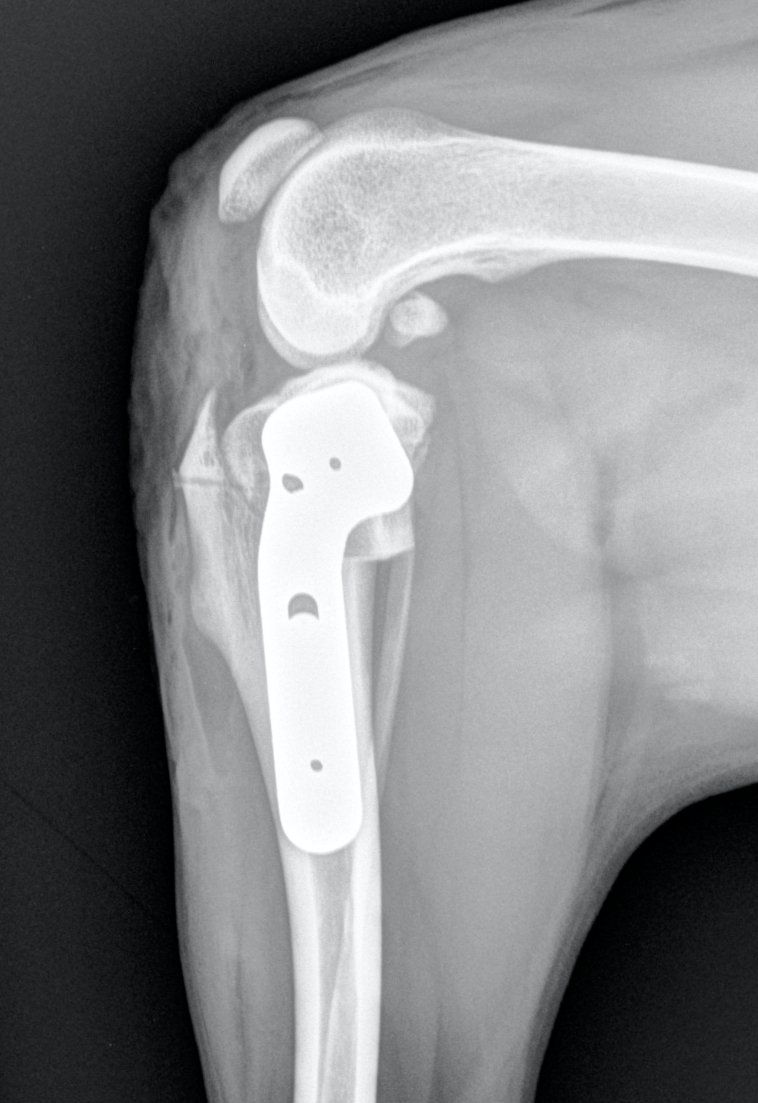

Fracture Salter-Harris sur un chaton Européen de 10 mois

Spike, chaton européen mâle de 10 mois, a été présenté en consultation pour boiterie du membre postérieur droit à la suite d'une chute depuis le 1er étage.

A la radiographie, une fracture de type Salter-harris 1 est diagnostiquée, avec déplacement de l'about discal.

Une réduction de la fracture par pose de 2 broches en croix a été réalisée.